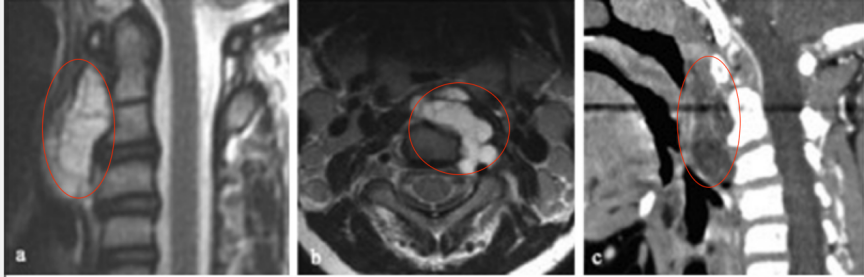

【图2(a)术前MR及CT显示,C1-3占位,提示嵴索瘤可能】

术后影像显示,经次全切术后左侧C2-C3神经孔有残留病变,于是教授及其团队为其执行综合治疗方案,并且制定了专属个性化放疗计划,结果显示她对70gy光子放疗反应良好,幸运的是,她的耐受性也很好,治疗顺利,放疗后残留病变明显变小,也无明显放疗副作用。

【图3术后MR显示肿瘤切除达95%以上,C2-C3神经孔内有小残留肿瘤(d,如箭头所示)】